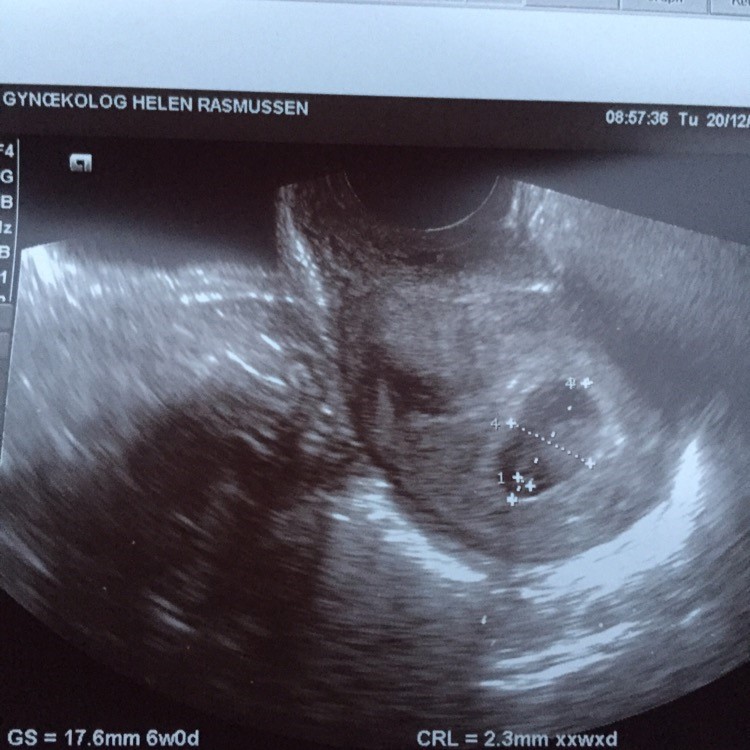

Jaaa du har nok ret. Det er dælme bare svært. Frygter virkelig bare at man går og regner med at man er gravid i flere uger og så er der bare ikke noget til scanningen. Hvad skal man være opmærksom på??

Kan virkelig godt forstå dig!! Har selv haft 2 Missed abortions, som også blev opdaget ved en tidlig scanning, men jeg synes ikke jeg har oplevet forskel i, hvordan mine symptomer var - har været meget mildt ramt alle gangene, så nok også derfor jeg ikke har mærket noget anderledes de gange jeg har mistet... Denne gang oplevede jeg kun ligamentsmerter i starten som symptom, så man behøver ikke mærke en hel masse og alting kan heldigvis stadig være i skønneste orden